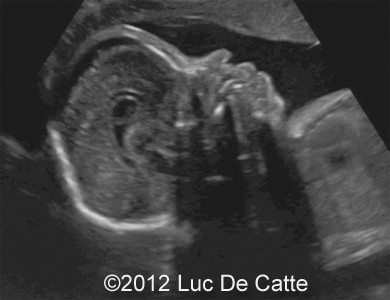

Image 1, 2:  A turricephalic or “tower shaped” skull and frontal bossing

COW_1

COW_1B

• Coronal and sagittal craniosynostosis leading to a turricephalic or “tower shaped” skull

• Prominent forehead (frontal bossing)

• Depressed nasal bridge

• Exophthalmos and prominent open eyelids

• Ocular hypertelorism

• Low -set ears